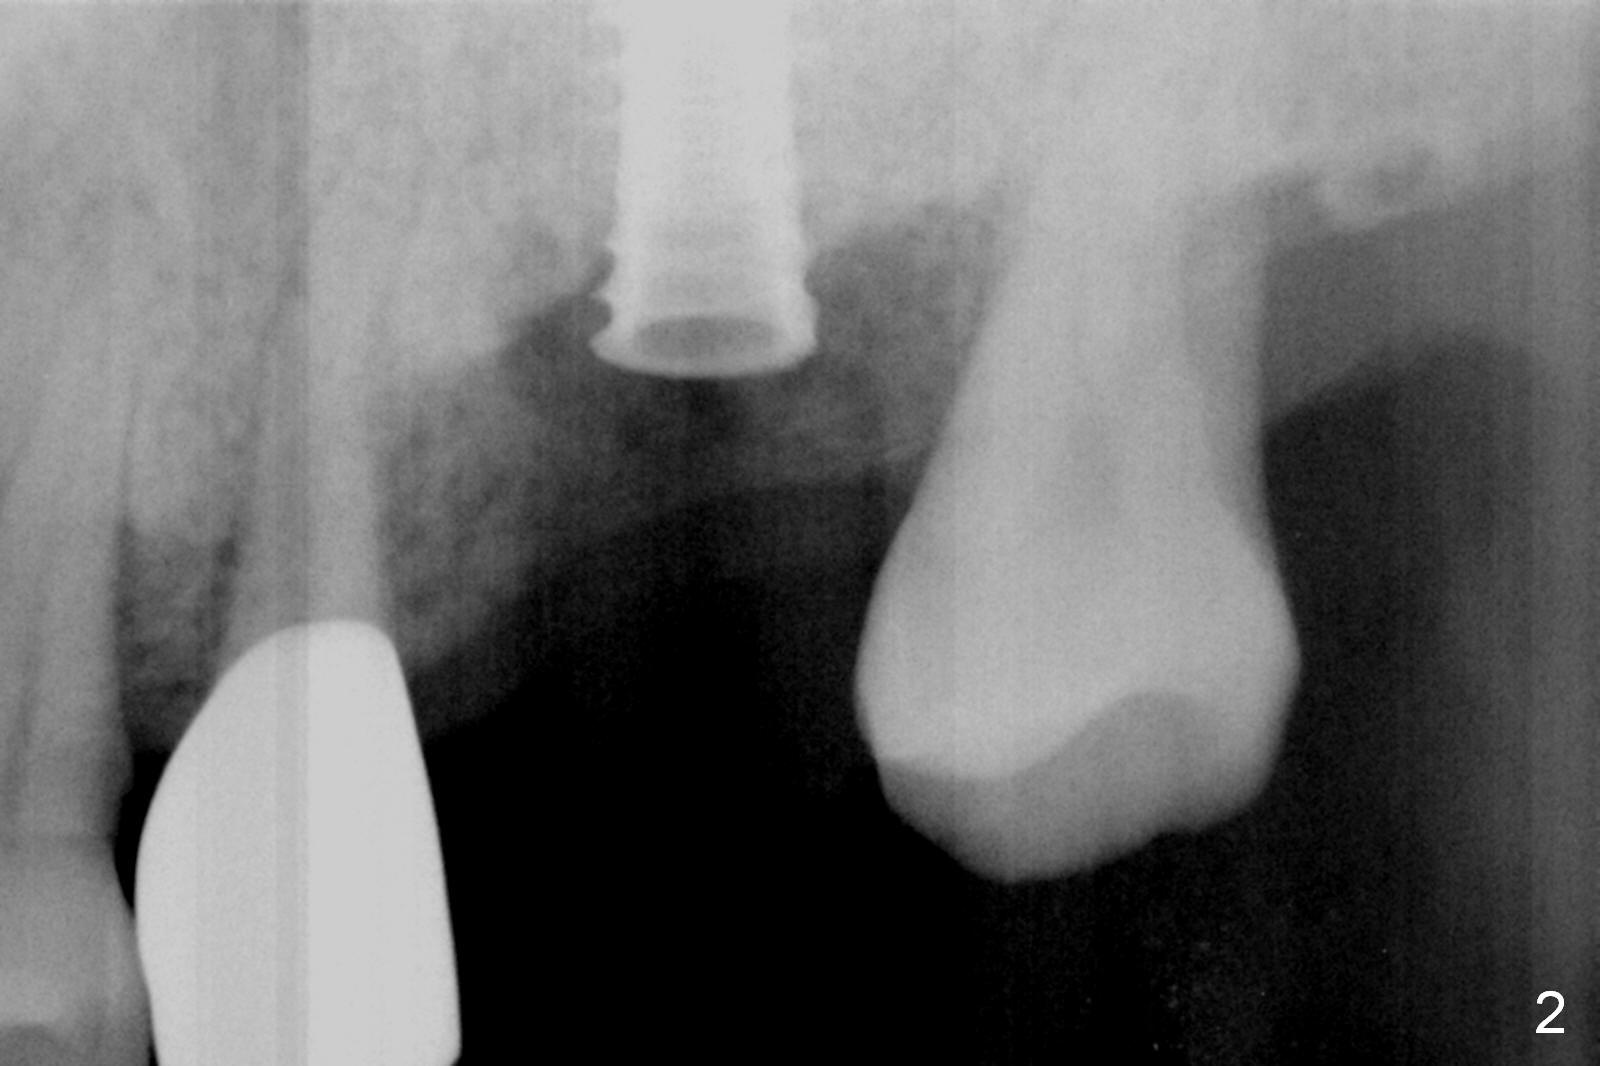

Preop exam show that the tooth #14 appears to be more severe than #18. When the former is extracted with forceps (not so easy), the mesial portion of the mesiobuccal root splits. The latter may be the reason for discomfort and one of the outcomes of advanced peridontitis. The septum is wide enough to use 4.3 mm Magic Drill (MD) following 1.6 mm pilot drill and Marking bur. A 5x13 mm IBS implant is placed apical to the mesial and distal crest and coronal to the septum (Fig.2,3). Insertion torque is ~ 35 Ncm. A 6.0x5.7(4) mm pair abutment is chosen over a 6.5 mm one, because the implant is placed somewhat distally (Fig.4,5). If the implant were placed more apically, the 4 mm cuff would be short for restoration. Allograft and autogenous bone harvested from the MD is placed around the coronal portion of the implant and the abutment cuff (*). Acrylic is spread around the abutment to hold the bone graft in place (without trimming).